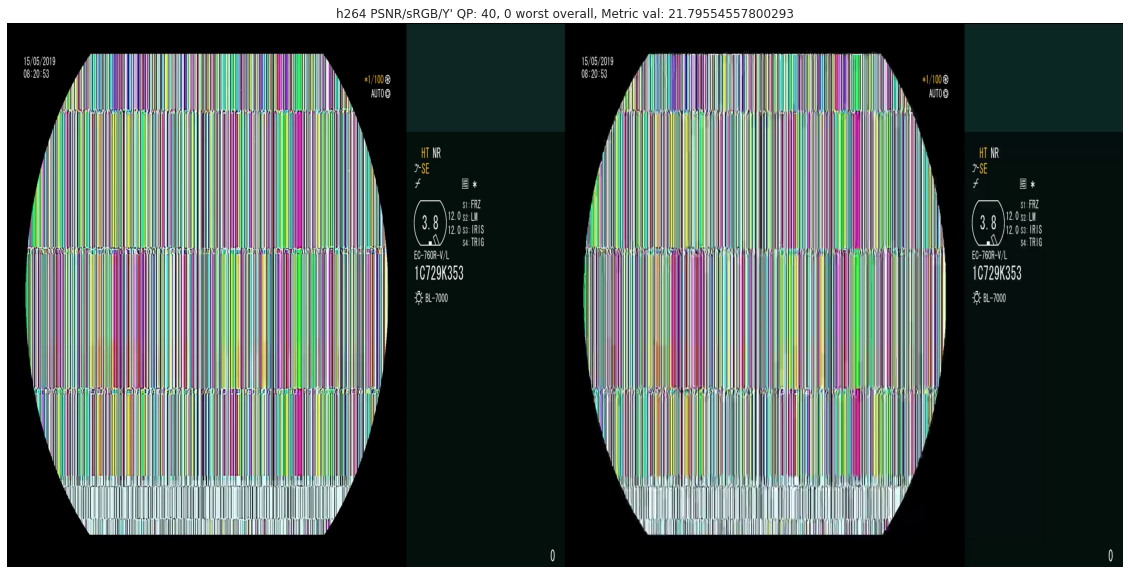

Compression quality: Figure 1 (middle) shows the compression rate versus frame quality distribution for H264 and HEVC. Importantly, we see that H264 and HEVC compress the most medically relvant frames statistically significantly worse: treating each QP value separately, a two-sided Kolmogorov-Smirnov test between distribution of PSNR-CbCr shows that the frame quality is lower for polyp frames than for all frames. For each QP value, , , H264 (HEVC) maximum p-value over all tests is (), mean test statistic (). For the same test with PSNR-Y, see the Appendix. Figure 2 top two rows show the lowest quality compressed frames inside the body according to PSNR-CbCr, with and without polyps (for the absolute worst quality compressed frames, see the Appendix).

A.3 Lowest quality compressed frames